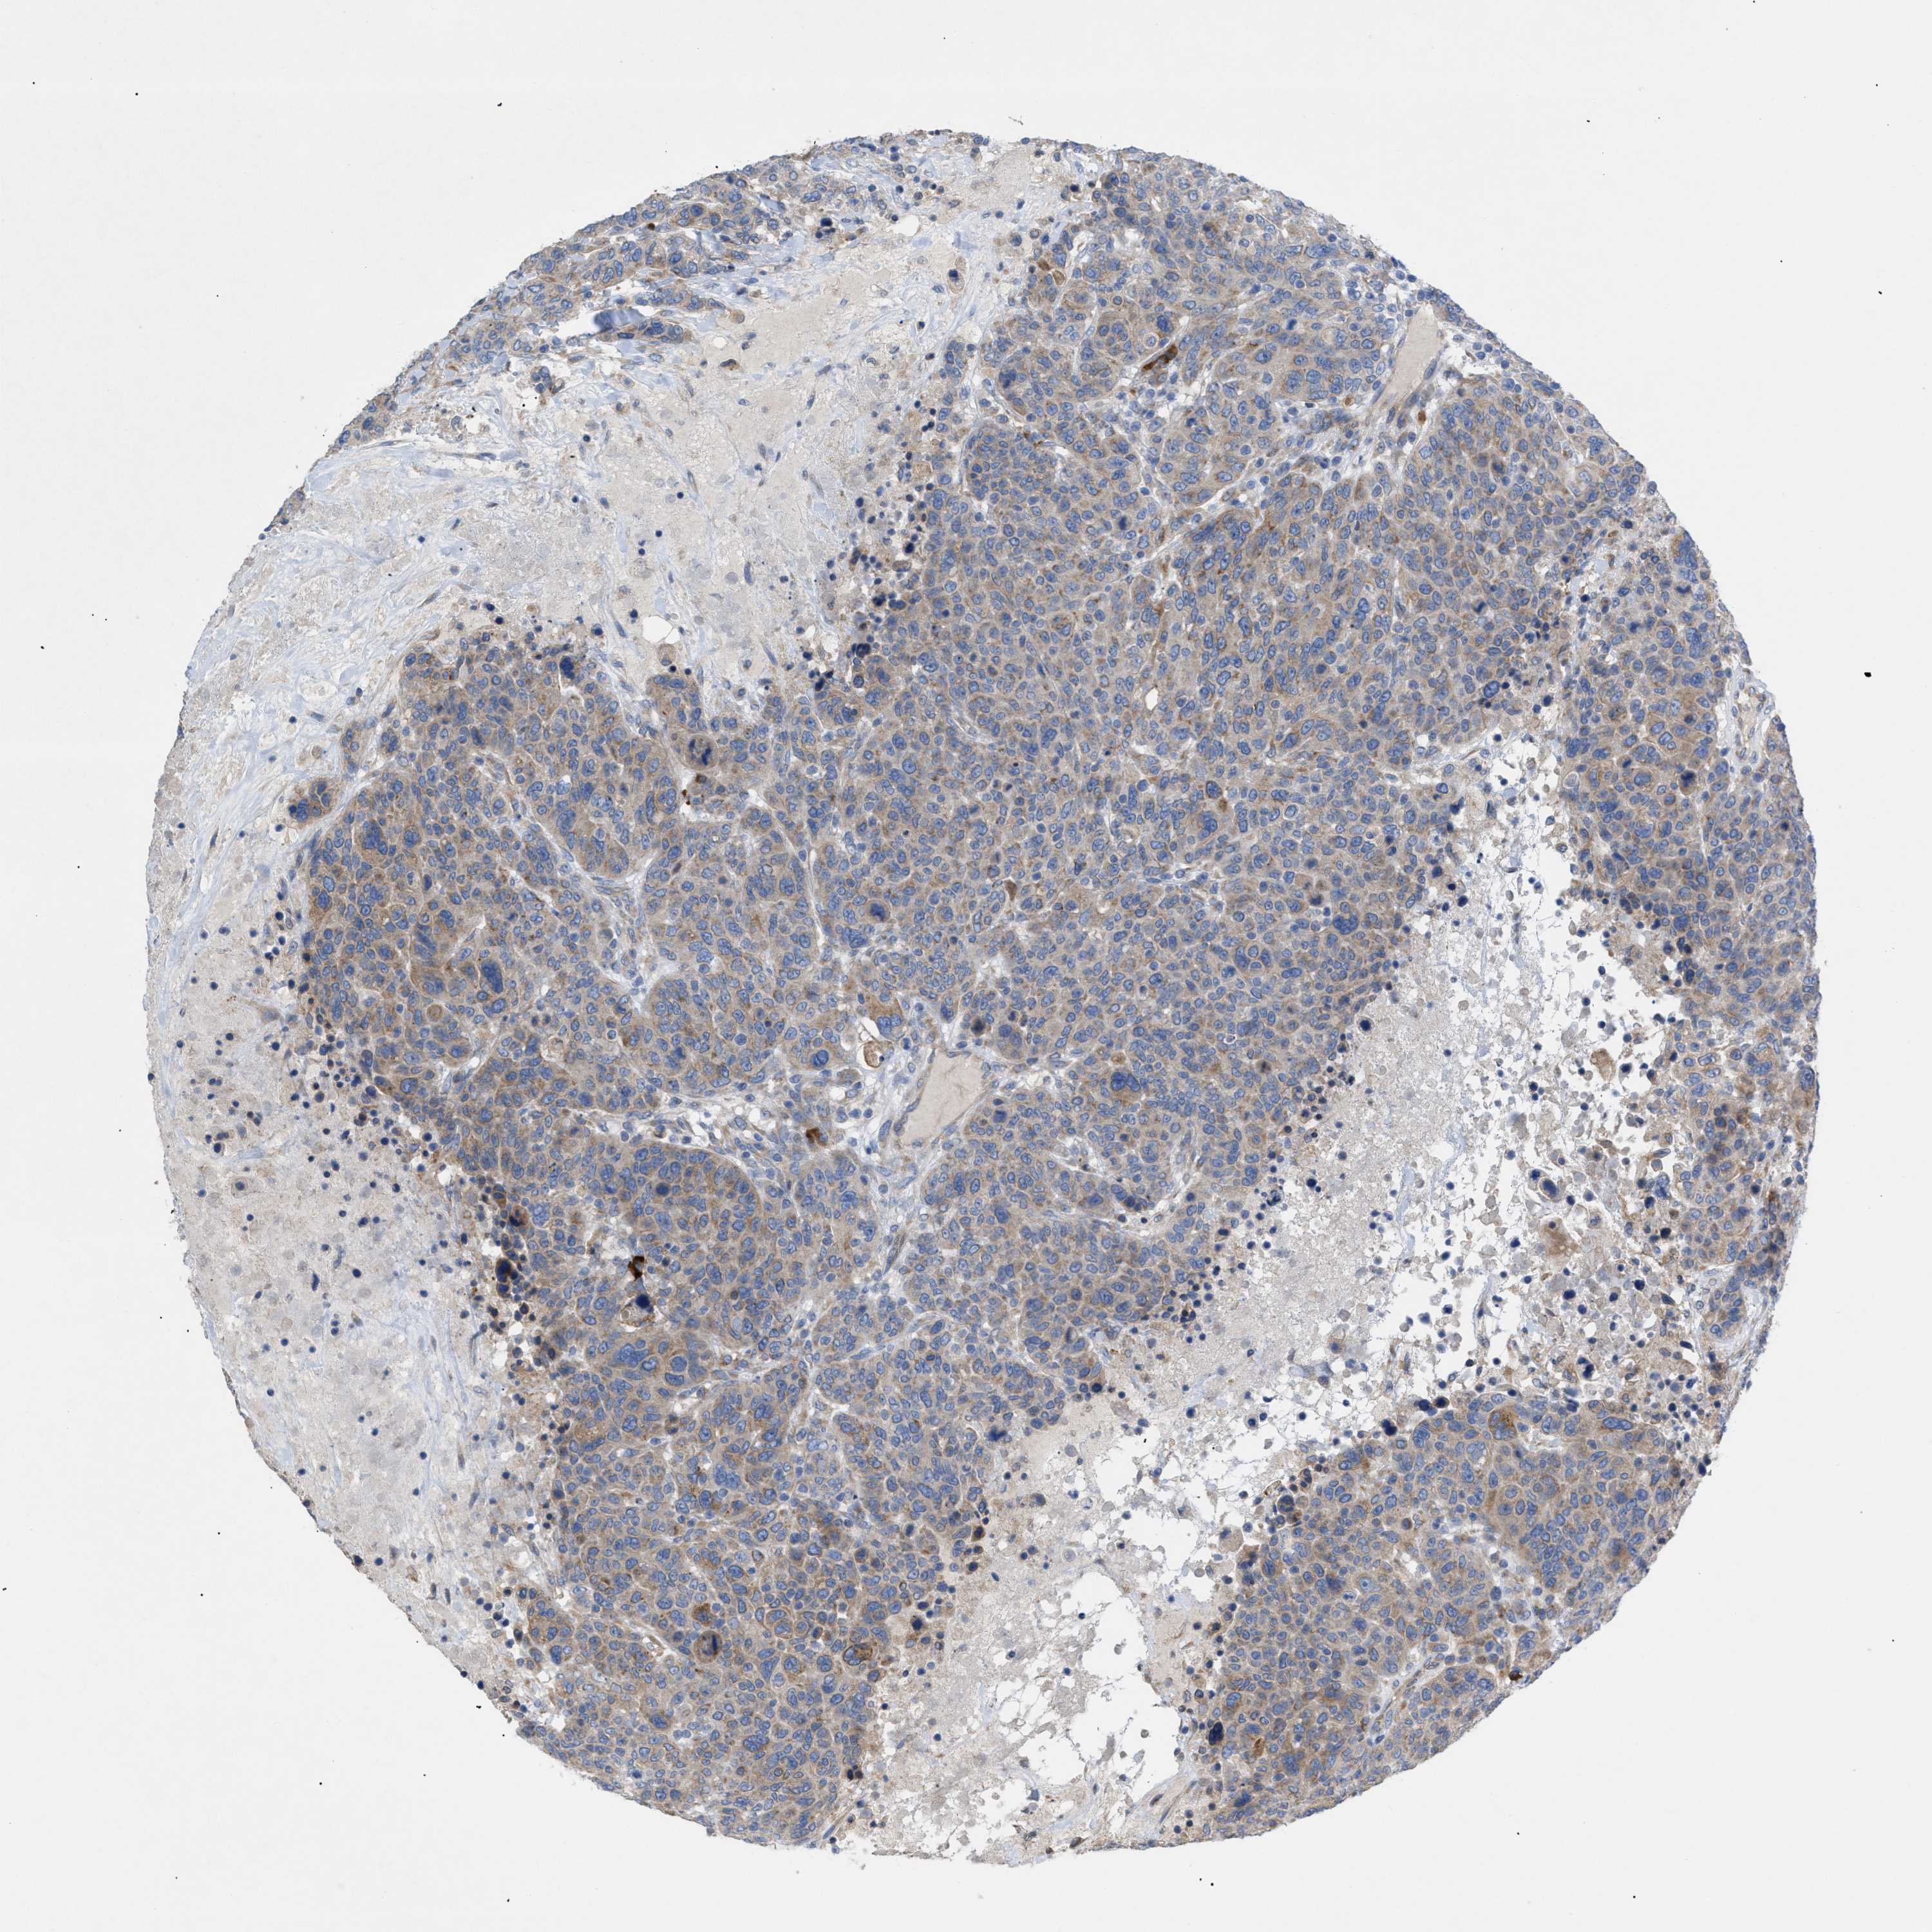

CANCER BREAST CANCER Show tissue menu

BRCA TCGA BRCA VALIDATION PROTEIN EXPRESSION